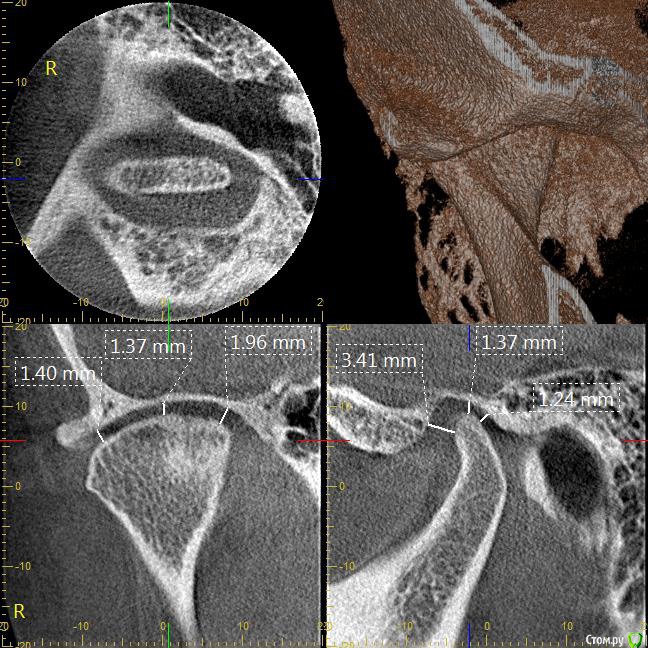

Мне 31 год. В детстве мне выбили верхний зуб 2-ку. Собираюсь лечиться брекетами, а потом вставлять имплант на место двойки. Но у меня есть еще проблеми с ВНЧС (с детства болит, хруст, щелчки), делала недавно КТ ВНЧС, диагноз артрит или артроз. Ходила к многим специалистам, все говорят разное. Надо ли проводить лечения капой моей дисфункции ВНЧС до установки брекетов или после установки брекетов?